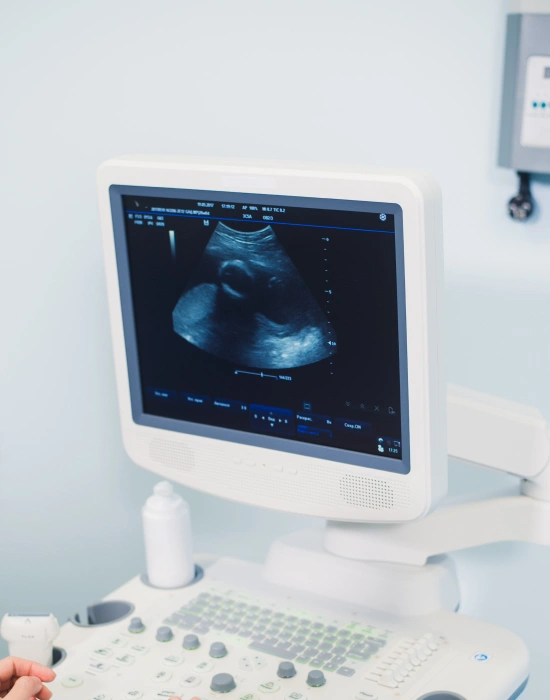

Ultrasound imaging is an essential diagnostic tool that allows veterinarians to evaluate your dog’s internal organs and soft tissues without invasive surgery. It’s a non-invasive procedure that provides real-time images of the body’s internal systems, helping the vet diagnose health issues quickly and with precision.

- Non-invasive and Safe: Ultrasound is a non-invasive procedure that does not require surgery or anesthesia. It’s safe for dogs of all ages, including senior dogs or those with pre-existing health conditions.

- Real-time Imaging: The ability to view internal organs in real time enables dynamic observations, helping make quicker, more accurate treatment decisions.

- Minimal Stress for Your Dog: Unlike invasive procedures such as surgery or biopsies, an ultrasound is a low-risk, low-stress procedure that most dogs tolerate well. There is no recovery time, and your dog can return to normal activities immediately.